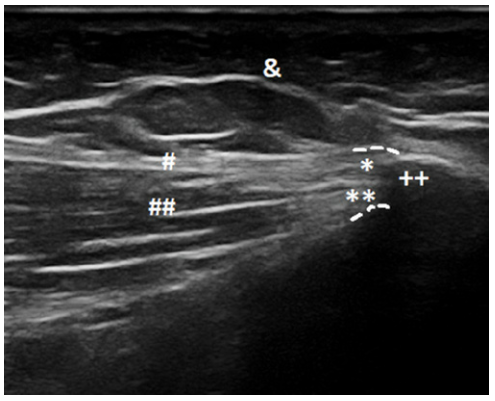

DOI: 10.15557/JoU.2018.0003 2018년 Journal of Ultrasonograph의 연구에 따르면, 건강한 사람의 이 부착부는 초음파상 하얗고 매끄러운 섬유 다발로 보입니다.

DOI: 10.15557/JoU.2018.0003 하지만 통증이 있는 환자의 경우 다음과 같은 변화가 관찰됩니다. 1. 부착부 비후: 힘줄이 퉁퉁 부어 두꺼워져 있거나, 2. 저에코 병변: 염증으로 인해 어둡고(Hypoechoic), 3. 골극 형성: 뼈 표면이 울퉁불퉁하게 튀어나와 있습니다.